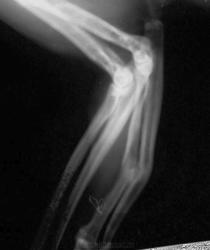

В возрасте одного года упал с высоты 8 этажа на газон, отделался оскольчатым переломом ср/3 диафизов лучевой и локтевой костей правой передней конености с угловым смещением.

Был интрамедуллярный остеосинтез. Через год извлечение стержня МОС. Снимков до и после операции к сожалению не сохранилось.

Данный снимок выполен через 8 лет, по другому поводу (рентген-неконтрастное инородное тело в гортани).

Выкладываю увеличенный фрагмент снимка и полный снимок.

Сейчас бодр и весел. Кончность с заметной угловой деформацией. Не болит, полностью функционирует.